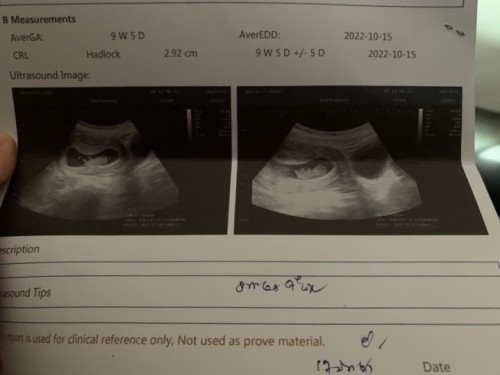

9w3d มีหัวใจมีแขนมีขาครบค่า 🥰 ลุงหมอบอกว่า น้องตัวยาว แล้วดิ้นเก่งมาก ชูมือชูเท้าใหญ่เลย ไม่มีการเขิลอายอะไรทั้งนั้น 🤣 (คิดในใจ คงจะสูงได้พ่อเค้าแหละ) มีการโบกมือทักทายคุณแม่คุณพ่อและคุณย่าด้วย แม่จะได้เห็นลูกทุกเดือนแล้วงับ 👶🏻🍼🤍 ปล:คุณพ่อและคุณย่าเห่อลูกเห่อหลานมาก 🤣🥰 #อัลตร้าซาวด์ครั้งแรก #ตื่นเต้น #ว่าที่คุณแม่มือใหม่ #ว่าที่คุณแม่

กำลังตั้งครรภ์